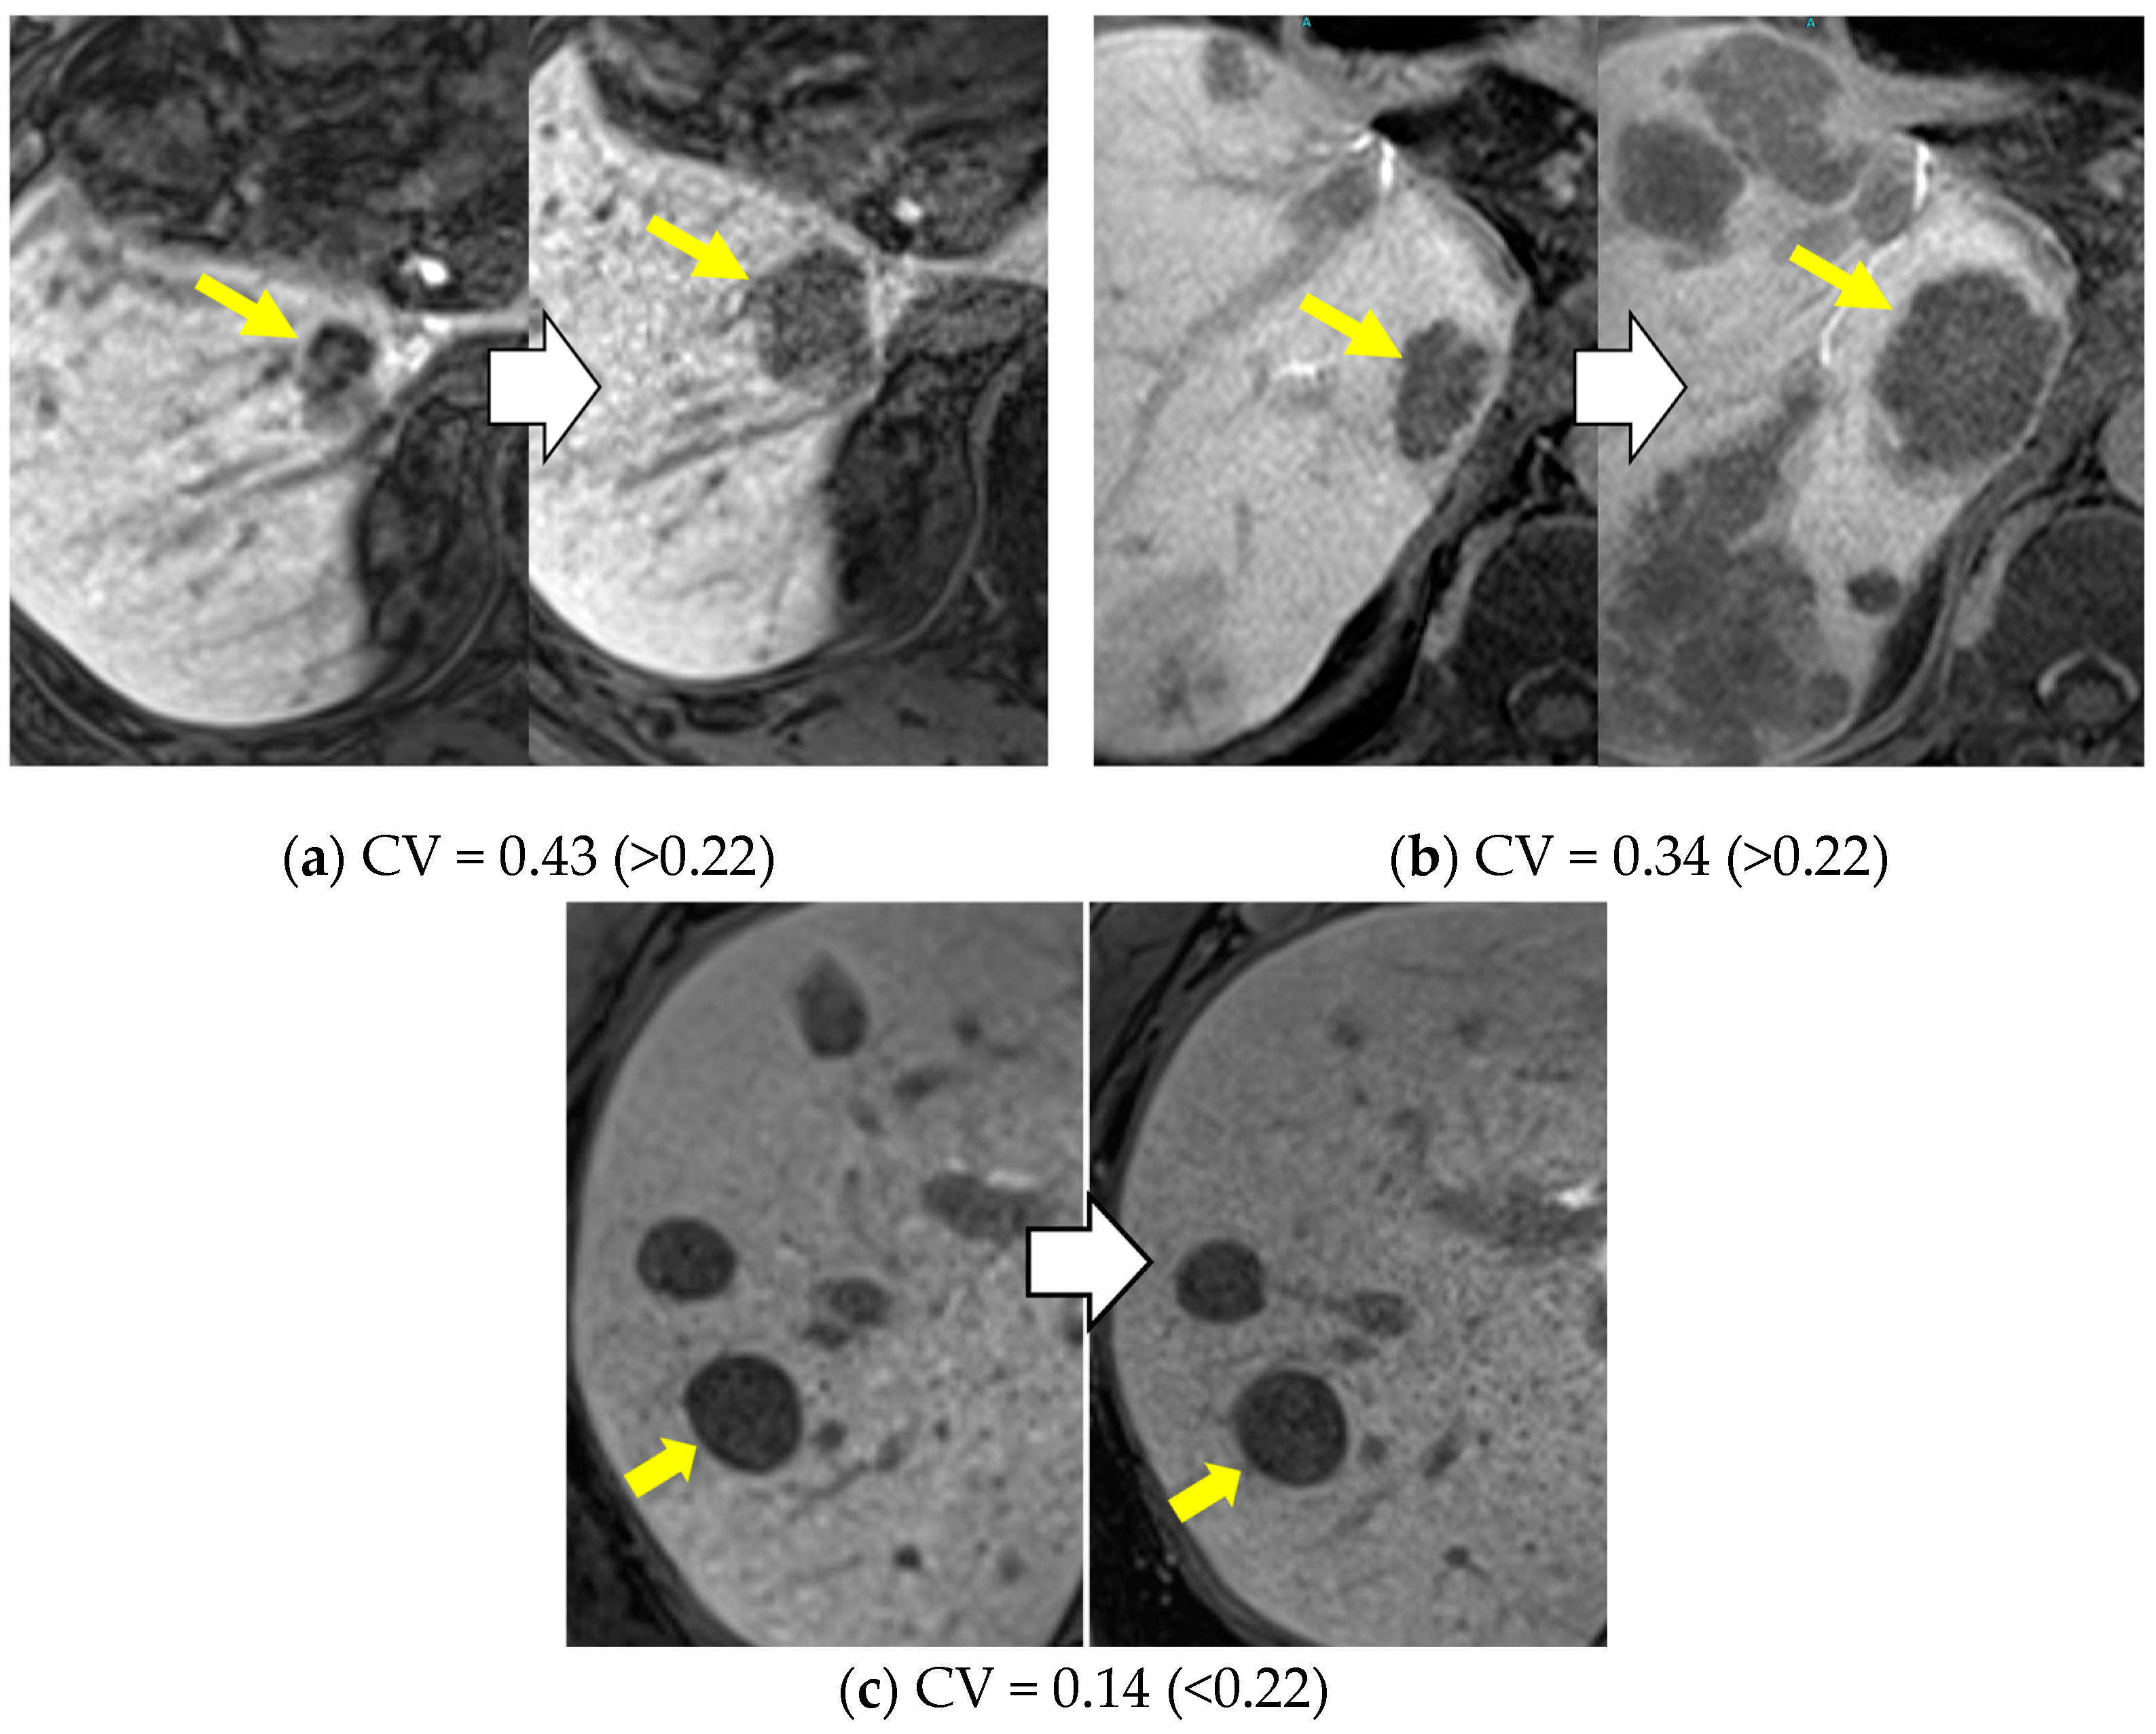

2.3. Imaging Analysis: CV